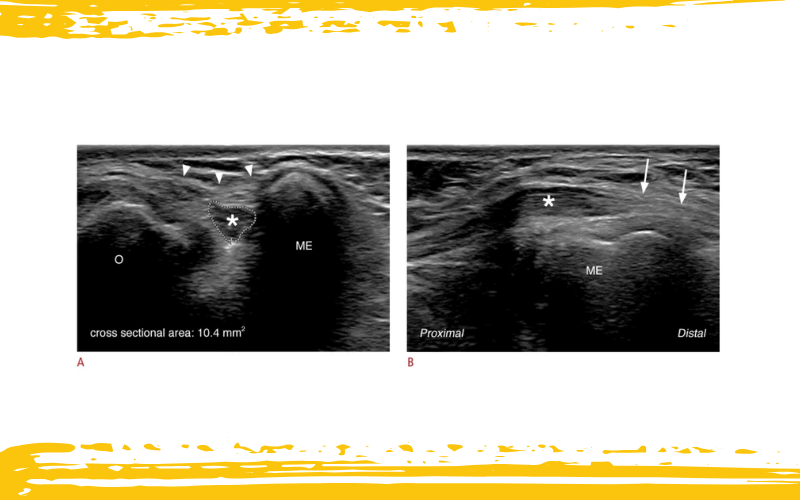

Imágenes ecográficas del codo posteromedial a nivel del túnel cubital en una mujer de 25 años con neuropatía cubital.

A. La vista ecográfica en eje corto a nivel del túnel cubital revela un nervio cubital aumentado de tamaño e hipoecoico (asterisco), situado entre el epicóndilo medial (ME) y el olécranon (O). El área de sección transversal del nervio cubital es de 10,4 mm². El retináculo del túnel cubital (puntas de flecha) se identifica como una estructura membranosa hiperecogénica que cubre el túnel cubital.

B. La vista ecográfica en eje largo del túnel cubital demuestra un aumento segmentario del calibre del nervio cubital (asterisco) en la porción proximal del túnel cubital, mientras que el nervio cubital distal muestra una apariencia fascicular hiperecogénica normal (flechas).

Y, ¿cuándo podemos decir que ese nervio está realmente aumentado? La literatura ofrece varios valores, pero hoy por hoy, un CSA de ≥10 mm² se considera un umbral diagnóstico confiable para el síndrome del túnel cubital. Este valor se basa en que raramente se supera esa cifra en individuos sanos, y ha demostrado una sensibilidad del 85% y una especificidad del 91%. Como los valores pueden variar según el sexo y el tamaño corporal, la comparación contralateral (lado sano vs lado afectado) puede aportar información valiosa en casos límite.